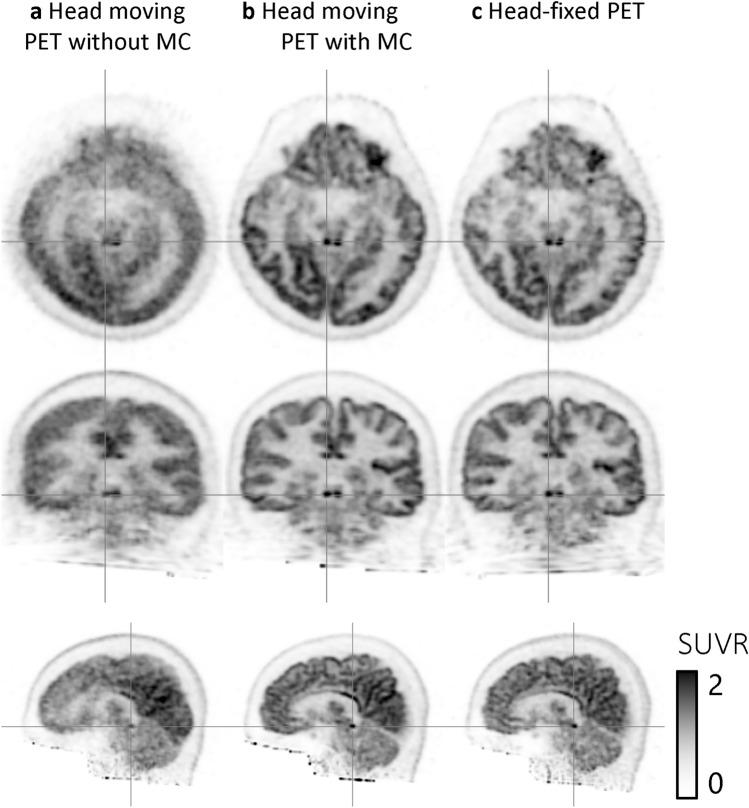

RESULTS

No difference was identified visually and statistically in SUVRs between the head-moving PET images with motion correction and the head-fixed PET images. One of the small nuclei, the inferior colliculus, was identified in the head-fixed PET images and in the head-moving PET images with motion correction, but not in those without motion correction. In the test-retest experiment, the SUVRs were well correlated (determinant coefficient, r = 0.995).

结果

校正后的头部运动 PET 与头部固定 PET 图像在 SUVr 上没有明显差异。在头部固定 PET 图像和校正后的头部运动 PET 图像中可以识别出一个小核,即下丘,但在未校正的头部运动 PET 图像中则无法识别。在测试-重测实验中,SUVr 相关性良好(决定系数 r=0.995)。